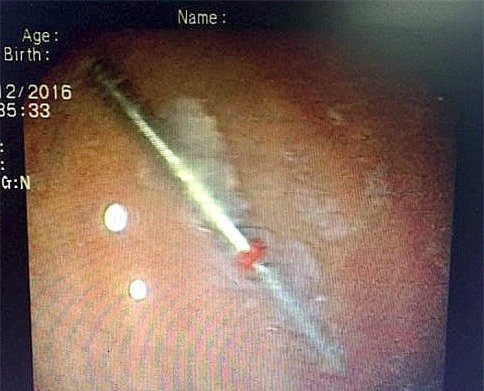

Sau khi khám răng, một nha sĩ không may làm rơi mũi khoan dài 3cm vào họng người bệnh khiến bà D.T.M.H. (56 tuổi, TP. HCM) phải nhập viện cấp cứu.